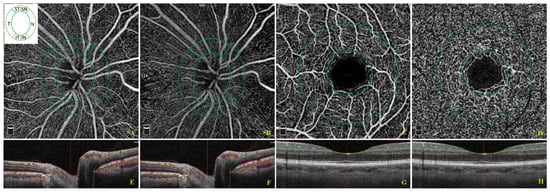

3.2. Analysis of Ophthalmological Parameters

| Without Hypertension | With Hypertension | ||||

|---|---|---|---|---|---|

| Mean ± SD | Median (Min to Max) | Mean ± SD | Median (Min to Max) | p Value * | |

| BCVA (LogMar) | 0.13 ± 0.3 | 0.03 (0 to 1.6) | 0.11 ± 0.2 | 0.03 (0 to 1.8) | 0.70 |

| IOP (mmHg) | 14.9 ± 3.4 | 14.4 (10 to 22) | 14.7 ± 3.1 | 14.5 (9 to 21) | 0.14 |

| GCC thickness (µm) | 99.2 ± 18 | 96.5 (65 to 237.8) | 95.4 ± 12.6 | 94.5 (44.7 to 180.1) | 0.04 |

| RNFL thickness (µm) | 97.6 ± 10.7 | 98 (62 to 128) | 95.5 ± 11 | 96 (57 to 127) | 0.06 |

| ONH peripapillary inferior temporal VD (%) | 63.7 ± 4.8 | 64.5 (46.2 to 71.9) | 62.2 ± 5.8 | 62.8 (38.9 to 72.3) | 0.02 |

| ONH inside Optic Disc VD (%) | 58.6 ± 8.2 | 59.4 (28.7 to 72.6) | 60.8 ± 6.4 | 62.1 (35.7 to 72.9) | <0.01 |

| RPC inside Optic Disc VD (%) | 38.7 ± 10.6 | 37.8 (13.3 to 67.2) | 42.9 ± 10.8 | 43 (13.3 to 67.2) | <0.01 |

| SSI | 61.3 ± 10.4 | 62 (34 to 87.6) | 62.6 ± 11.1 | 63.7 (2.1 to 87.6) | 0.20 |